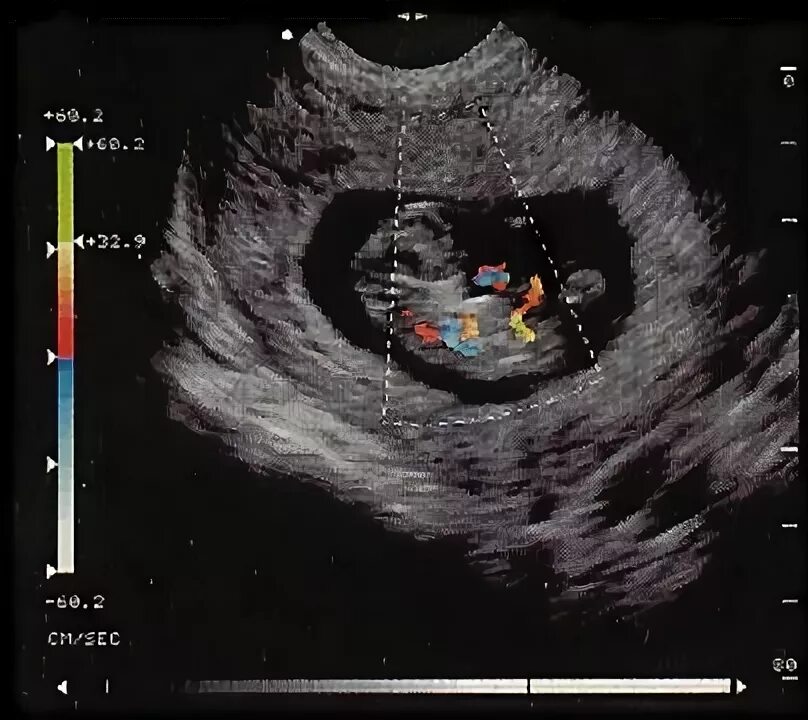

Что такое допплер беременных